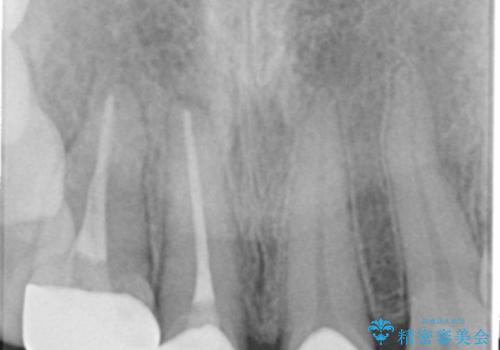

- 1週間ほど前に自転車で転倒して前歯をぶつけた後、歯の色が変わっていることが気になり受診された方です。診察の結果、失活及びエナメル質に多数の亀裂が認められたため、根管処置およびセラミッククラウンによる治療を行いました。元々右上2番目の歯の形が気になっていたとの事で、左右対称の形に近づけるように補綴しました。

左上1番目の歯は失活していませんでしたが、歯の表面に多数の亀裂が認められました。患者様のご希望により、前歯3本をまとめて補綴処置することとなりました。土台となる歯質の色が異なる状態でしたが、熟練した技工士さんの技術により3本とも同じ色味になるように仕上げていただきました。色味、形態ともに自然な被せ物に大変喜んでいただけました。